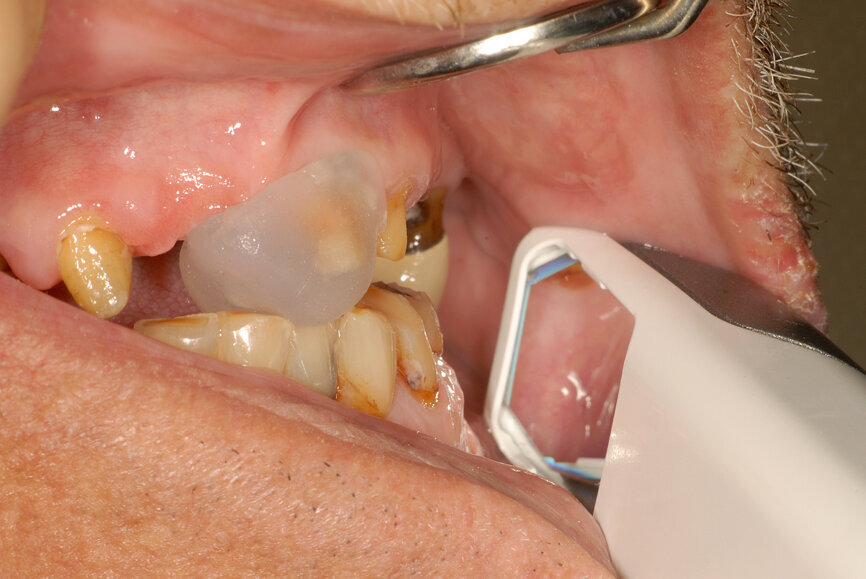

Fig. 22: Analogue recording of centric relation using a composite device to stabilise the mandible and polyvinylsiloxane recording paste.

Fig. 23: Analogue recording of centric relation using a composite device to stabilise the mandible and polyvinylsiloxane recording paste.

Fig. 24: Centric relation recording using an intra-oral scanner while the mandible is stabilised by a leaf gauge at the desired vertical dimension of occlusion.

The technique for recording the CR position can be performed using analogue (Figs. 22 & 23) or digital methods (Figs. 24–27).